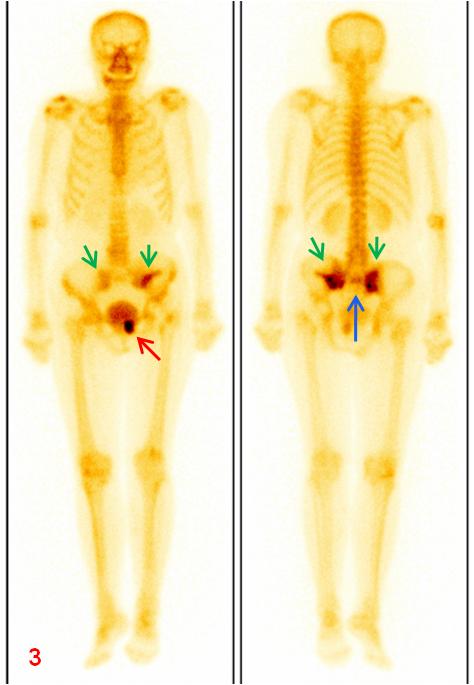

老年女性,1年前因直腸惡性腫瘤于外院行放射治療,此次常規(guī)復(fù)查平掃CT示骶骨及左側(cè)恥骨密度不均勻,左側(cè)恥骨骨質(zhì)斷裂;平掃M(jìn)R示雙側(cè)骶骨翼、左側(cè)髂骨及左側(cè)恥骨異常信號(圖1、2);為進(jìn)一步明確診斷行全身骨顯像ECT檢查(圖3)。

圖3全身骨顯像:雙側(cè)骶髂關(guān)節(jié)(綠箭)、骶骨(藍(lán)箭)及左側(cè)恥骨(紅箭)放射性異常濃聚。